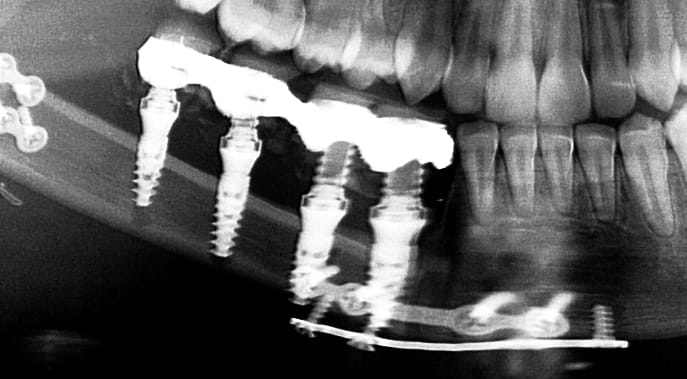

Bien sur que sur cette pano le col des 2 implants distaux son bien supra osseux et les mésiaux et surtout le second infra-osseux mais indéniablement les spires apicales semble avoir perforés la corticale, alors !!!

Une pano est elle faite pour contrôler un volume ???

En montrant la partie de la greffe positionné en lingual il n'ya pas de perforation et de spires apparente, Pourquoi ???

Stop bouboule, reprend le truc à la base. T'es partie sur affirmation d'hokusai :

"bin si tu trouves qu ils sont bien posés c est cool 👍

l implant le plus distal avec ces 5 spires en dehors de l os... chapeau l artiste.

une gestion de la profondeur de forage aux petits oignons..."..."t aurais du faire carriere chez pinder"

1 / Les spires c'est à l'apex > voila pourquoi la photo de la greffe montrant le coté où ces spires pourraient apparaitre

2/ Les spires des implants en mésial qui semblent perforer la corticale sur la pano ne le font pas en clinique et tu voudrais que je ne me pose pas de question ?

3 /si tu as une explication, je suis preneur parce que l'autre compte sur toi